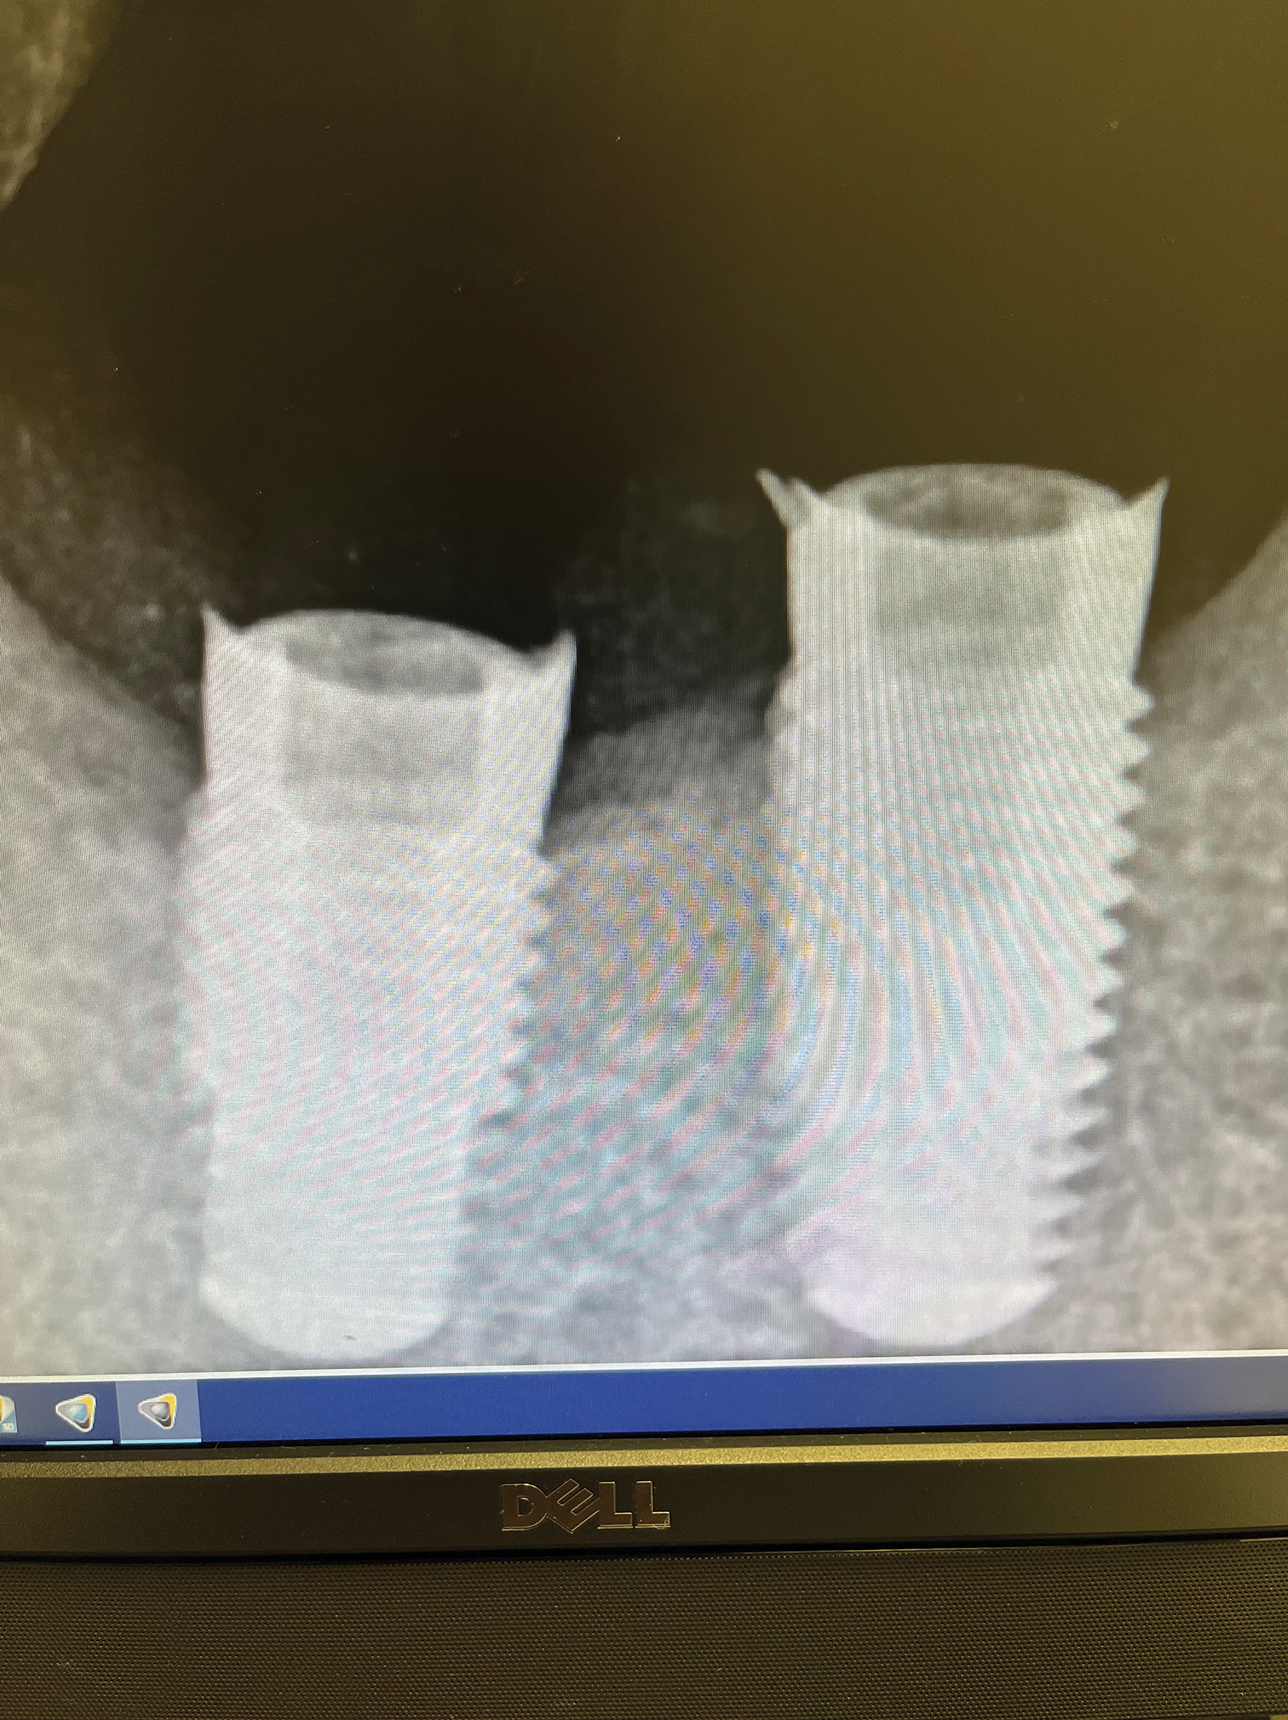

(3.) Specialized drills permit osteotomy preparation and implant placement into vital cancellous bone, which is more vascular than cortical bone and can help to reduce bone loss.

Figure 3

(4.) Specialized drills permit osteotomy preparation and implant placement into vital cancellous bone, which is more vascular than cortical bone and can help to reduce bone loss.

Figure 4

(5.) Complications related to misfitting prostheses can include fracture of the prosthesis, bone loss around implants, and fracture of the implant body requiring removal.

Figure 5

(6.) Complications related to misfitting prostheses can include fracture of the prosthesis, bone loss around implants, and fracture of the implant body requiring removal.

Figure 6

(7.) Complications related to misfitting prostheses can include fracture of the prosthesis, bone loss around implants, and fracture of the implant body requiring removal.

Figure 7